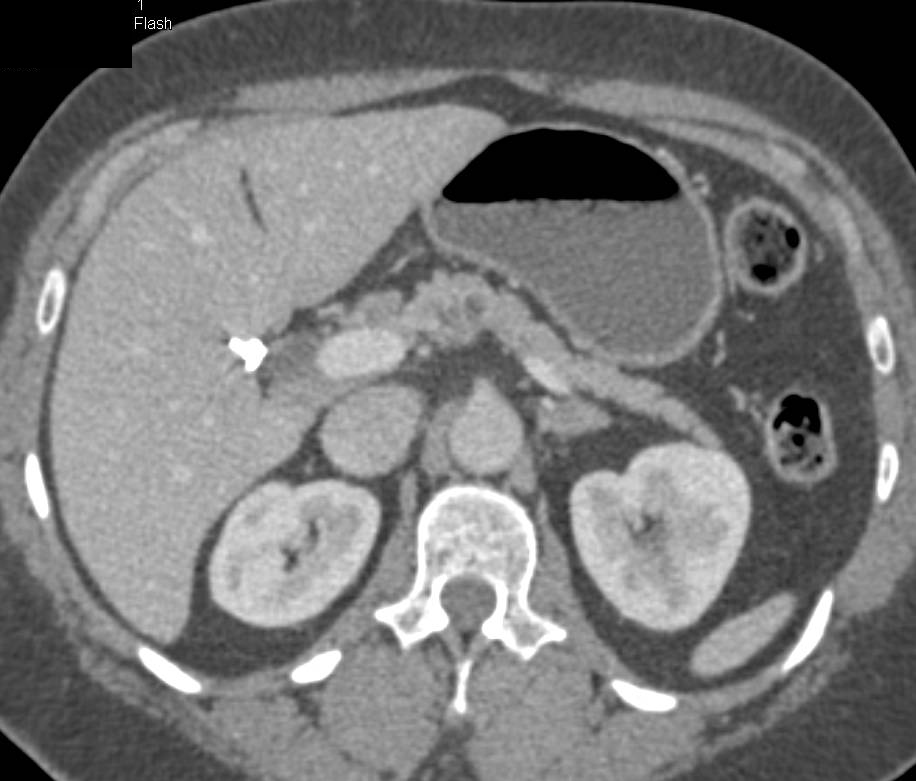

Nodes Near Head of Pancreas